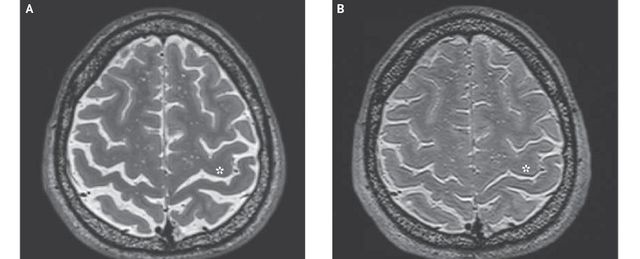

Дослідження було фінансовано NASA і воно торкнулося 34 космонавта. У кожного суб'єкта мозок був відсканований за допомогою функціональної магнітно-резонансної томографії двічі, до місії і після повернення на Землю. Результати сканування були надіслані нейрорадіологам для інтерпретації, при цьому жоден з фахівців не знав кому належать знімки.

З 18 космонавтів, які тривалий час перебували на МКС, у 17 були знайдені ознаки звуження центральної частини мозку, те ж саме було знайдено всього у трьох людей, які виконували короткострокові польоти. Загальний зсув головного мозку вгору виявили у 12 космонавтів з тривалими місіями і не виявлений у космонавтів, які виконували короткі польоти.